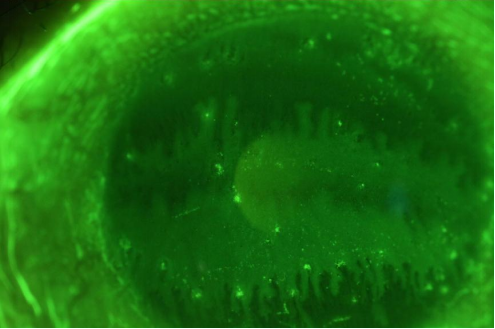

H女士眼前节照片:可见眼红充血,角膜凸起处有荧光染色